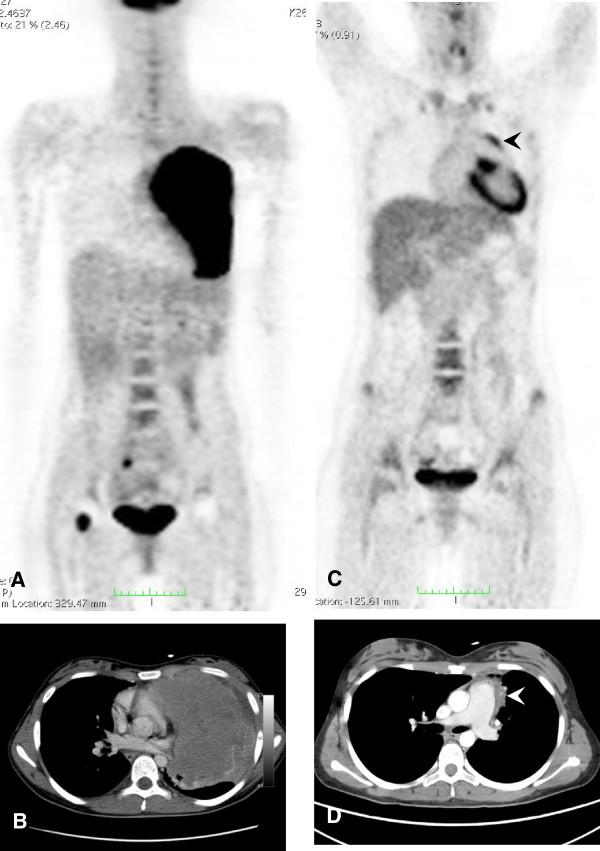

This study is to evaluate the predictive value of FDG-PET (PET) in pediatric and adolescent patients suffering from non-Hodgkin lymphoma (pNHL) in comparison to information provided by conventional imaging methods (CIM).

Imaging was performed at baseline and at interim (after 2 cycles of chemotherapy). The response assessment in PET was carried out visually and semi-quantitatively, the latter one by use of percentage decrease in SUVmax from baseline to interim (ΔSUVmax). The PET-based results were compared to the findings by CIM. Progression-free survival (PFS) was analyzed using Kaplan-Meier curves (KM) and log-rank test.

The final study included 16 patients (mean follow-up time, 60.2 months (range, 4.0 to 85.7 months)). Relapse occurred in four patients. Visual PET compared to CIM revealed higher sensitivity (3/4 vs 1/4) and NPV (6/7 vs 10/13), and equal PPV (3/9 vs 1/3), but lower specificity (6/12 vs 10/12) and accuracy (9/16 vs 11/16). False-positive findings in PET at interim were predominantly observed in patients presenting bulky disease (5/6), whereas CIM was true-negative in all of these cases. KM analyses revealed no significant differences in 5-year PFS neither for CIM (76.9% vs 66.7%; p = 0.67) nor for visual PET (85.7% vs 66.7%; p = 0.34) nor for ΔSUVmax (88.9% vs 57.1%; p = 0.12).

The predictive value of iPET in pediatric patients suffering from NHL was limited due to considerably high amount of false-positive findings, especially in patients suffering from bulky disease. However, due to our limited sample size, final conclusions cannot be drawn and, thus, call for further evaluation of PET in pNHL in larger and more homogenous patient series.

本研究旨在评估 FDG-PET(PET)在儿科和青少年非霍奇金淋巴瘤(pNHL)患者中的预测价值,并与常规影像学方法(CIM)提供的信息进行比较。

在基线和中期(化疗 2 个周期后)进行影像学检查。通过视觉和半定量方法进行 PET 反应评估,后者使用 SUVmax 从基线到中期的百分比下降(ΔSUVmax)进行。将基于 PET 的结果与 CIM 的结果进行比较。使用 Kaplan-Meier 曲线(KM)和对数秩检验分析无进展生存期(PFS)。

最终研究纳入 16 例患者(中位随访时间为 60.2 个月(范围为 4.0 至 85.7 个月))。4 例患者复发。与 CIM 相比,视觉 PET 显示出更高的敏感性(3/4 对 1/4)和阴性预测值(6/7 对 10/13),相同的阳性预测值(3/9 对 1/3),但较低的特异性(6/12 对 10/12)和准确性(9/16 对 11/16)。中期 PET 的假阳性发现主要见于存在巨大肿块的患者(5/6),而 CIM 在所有这些情况下均为真阴性。KM 分析显示,无论是 CIM(76.9%对 66.7%;p=0.67)还是视觉 PET(85.7%对 66.7%;p=0.34)或ΔSUVmax(88.9%对 57.1%;p=0.12),5 年 PFS 均无显著差异。

由于存在大量假阳性发现,特别是在患有巨大肿块的患者中,iPET 在儿科 NHL 患者中的预测价值受到限制。然而,由于我们的样本量有限,无法得出最终结论,因此需要在更大、更同质的患者系列中进一步评估 PET 在 pNHL 中的应用。